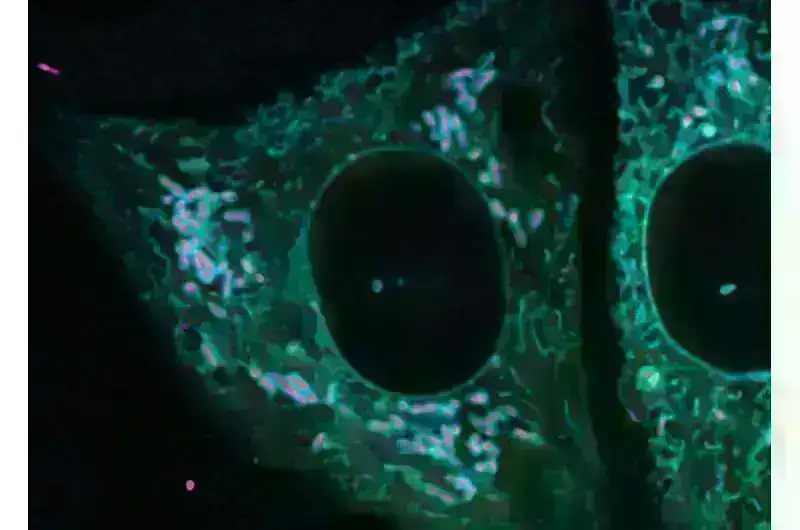

Görünməz ittifaqlar: Bakteriyalar və hüceyrələr cazibədar əlaqələr yaratdıqca krallıqlar toqquşur

Biologiya dərsliklərində endoplazmik retikulum çox vaxt nüvənin yaxınlığında fərqli, yığcam orqanoid kimi təsvir edilir və adətən protein alveri və ifrazatdan